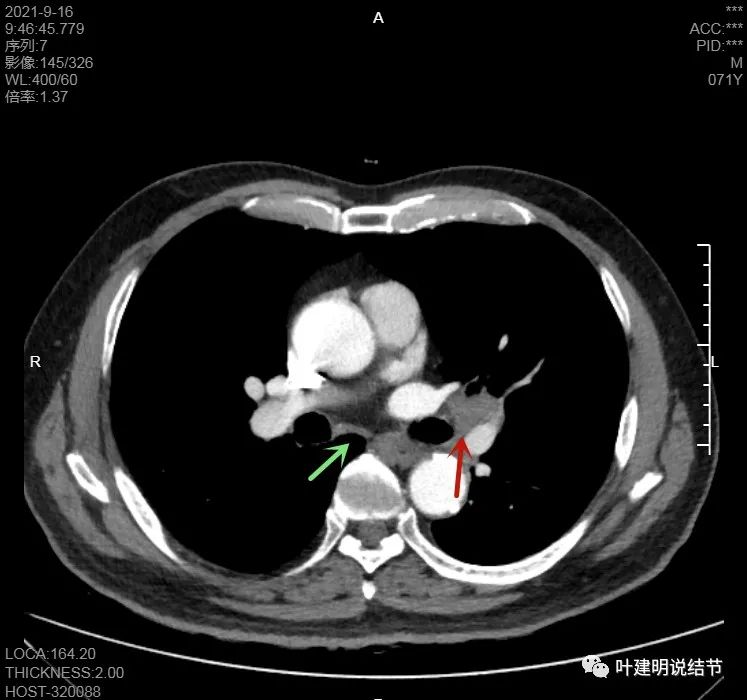

上图示病灶在左下叶,红色所指的与绿色箭头所指的是两个病灶,不相连的,实性结节